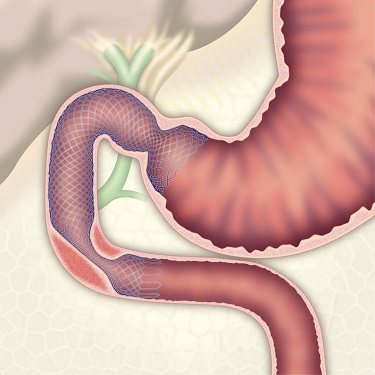

胃・大腸などの内視鏡検査とは異なり、膵臓・胆道では内視鏡的逆行性膵管胆管観察法(通称ERCP)というX線検査などを組み合わせた方法が行われます。十二指腸までスコープを進め、その先は内視鏡の先端から造影カテーテルという細いチューブを胆管や膵管に挿入して、造影剤を直接注入し、レントゲン写真を撮影することで、胆嚢や胆管及び膵管の異常を詳しく調べる検査です。同時に胆道膵癌の病変細胞診断や胆道閉塞のステント治療、胆管結石・膵石の治療にも応用されています。また、当院では、胃・胆道・膵臓切除手術後で、通常ERCPスコープでは乳頭に到達できない症例に対しては、小腸バルーン内視鏡を使ってERCPを行っております。

内視鏡的総胆管結石除去術

内視鏡的ステント留置術

胃切除後バルーン内視鏡ERCP

内視鏡的逆行性胆嚢ドレナージ(ERGBD)

胆石性胆のう炎には手術もしくは経皮的に胆嚢にチューブを留置する経皮経肝胆嚢ドレナージ術(PTGBD)や経皮経肝胆嚢穿刺吸引術(PTGBA)を行いますが、高齢化に伴い血液をサラサラにするお薬を複数飲んでいる方も多く、出血が危惧される場合や腹水がたまっている方、腹部超音波で胆嚢が見えない方の胆のう炎にも内視鏡的逆行性胆嚢ドレナージ(ERGBD)を施行し低侵襲で治療を行っています。